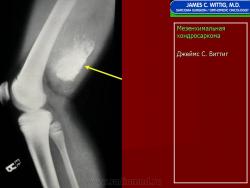

Рентгенологическое изображение при мезенхимальной хондросаркоме не обладает специфичностью и во многом сходно с обычной классической хондросаркомой, представлено литическим очагом без четких границ.

Рентгенологическая картина довольно разнообразная: это литические очаги деструкции, вздувающие кость, иногда с ячеистым или остатками ячеистого строения, наличием остатков от неполностью разрушенных костных структур, иногда с участками обызвествления и окостенения. При околокостном расположении опухоли бывает виден различной интенсивности очаг в мягких тканях с более равномерным или очаговыми формами обызвествления и окостенения с нечеткими контурами, прилежащий кости или охватывающий ее.